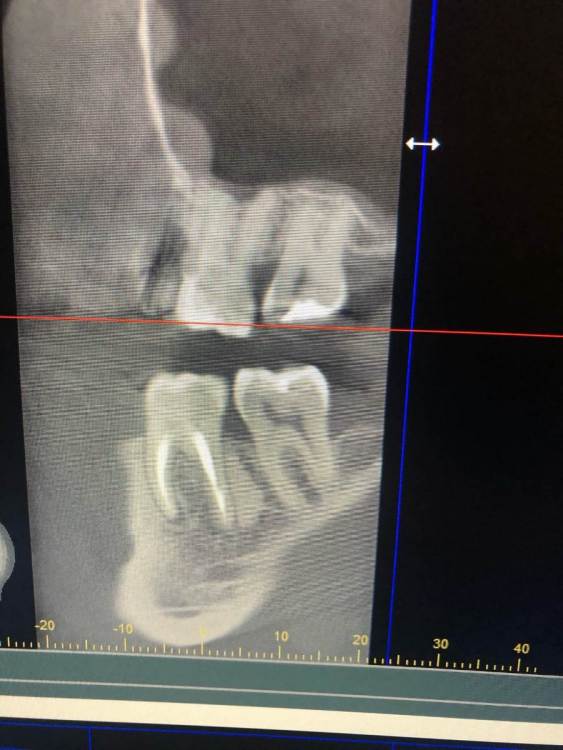

Периодонтит 4.6 с лизисом межкорневой перегородки

Немой некроз пульпы после лечения кариеса, болей не было, результат спустя 1 год и 8 месяцев, три посещения(кальций, пломбировка каналов, реставрация) кюретаж в данном случае не делал. Есть видео кт -